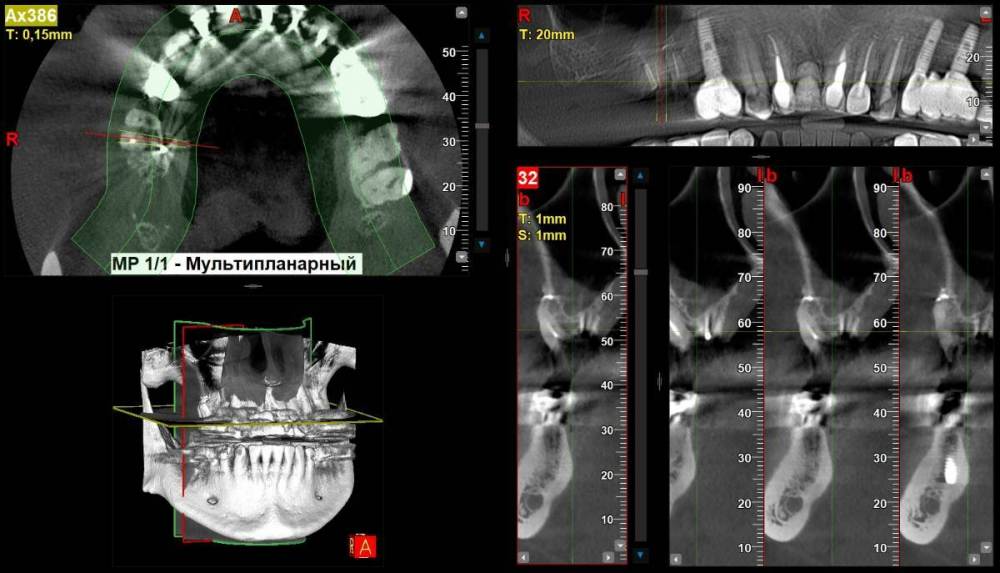

1) Зуб 16 лечен давно в 90х  ( возможно резорцин-формалином), на нем была пломба со штифтом которая сломалось вмсете со стенкой и штифтом. Зуб приговаривают к удалению.

Возможно ли использоавть этот корень под культевую вкладку и коронку и какой прогноз на такое восстановление?

Если удаление неизбежно, то какие варианты имплантации возможны очень желательно без открытого синус лифтинга. ( открытый синус лифтинг пугает осложнениями и долгой реабилитацией).

1. Зуб 16 удалять вне всяких сомнений. Закрытый или открытый синус-лифтинг? Решение будет принимать хирург, который будет вас оперировать.

16_1.thumb.jpg.d36ccf60c6da549ac9743c7b8c3456da.jpg

16_2.thumb.jpg.459fb3335e38209cef01f2895e775db4.jpg